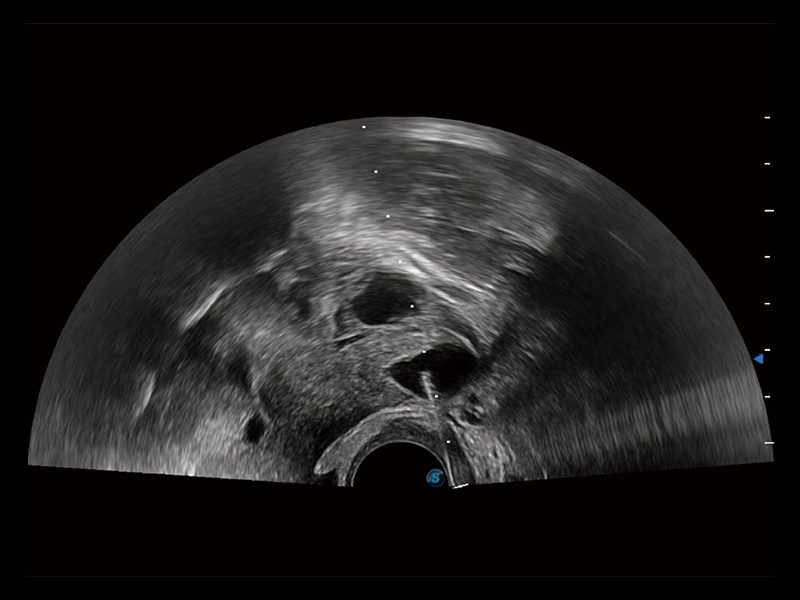

“生育问题”即关系民族复兴,也关系亿万家庭的幸福。随着婚育年龄推迟、社会压力增加等因素,越来越多人群也面临着“生不出、生不好”的问题。辅助生殖作为治疗不孕不育最有效的方法之一,也逐渐成为育儿新希望。而超声检查能为生殖需求人群的初诊评估提供宝贵的信息。 P20 Elite是球速体育入口匠心打造的一款生殖应用型彩超。她继承球速体育入口高端极光平台,突破性地将多款新型芯片及硬件模块进行整合,均衡了高端系统性能与小巧灵动机身。P20 Elite卓越的图像质量搭载专科探头,旨在为您提供全面的辅助生殖解决方案。

P20 Elite配备了丰富的生殖探头群和临床应用功能,在卵泡监测、穿刺取卵、胚胎移植、妊娠确认等领域,为生殖需求人群提供了新的临床机会,重新定义高端超声如何应用于生殖健康检查。